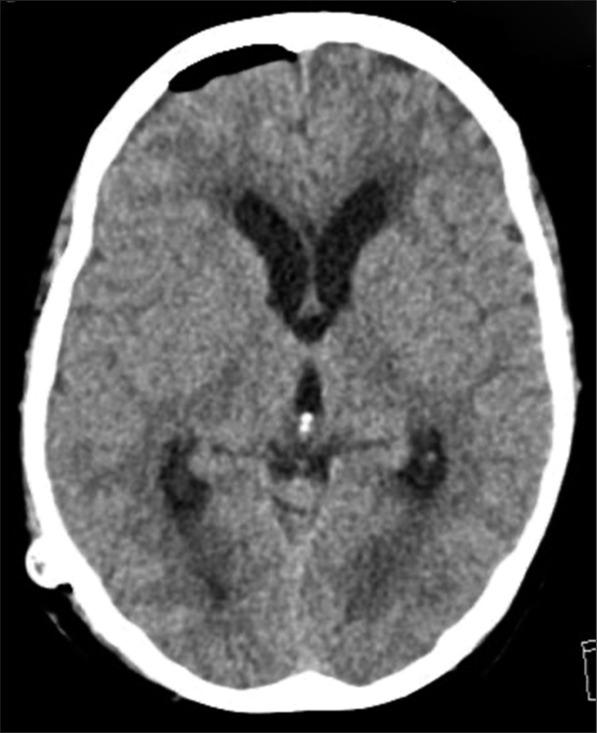

CASE DESCRIPTION

The case describes a 49-year-old Filipino woman with a history of hypertension who presented with symptoms strongly suggesting KBS following subarachnoid hemorrhage, including behaviors such as hyperorality, hypermobility, placidity, hypermetamorphosis, and hypersexuality along with memory disturbance. She was managed as a case of brief psychotic disorder initially with olanzapine, then on the second presentation as a case of delirium with risperidone.

该病例描述了一名49岁有高血压病史的菲律宾女性,蛛网膜下腔出血后出现强烈提示KBS的症状,包括口欲亢进、多动、平静、变换症和性欲亢进等行为以及记忆障碍。她最初被当作短暂性精神病性障碍病例用奥氮平治疗,第二次就诊时被当作谵妄病例用利培酮治疗。